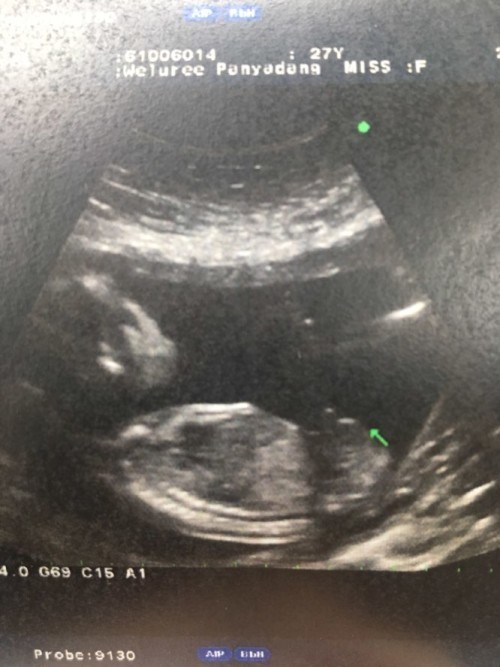

ขออภัยหากรูปภาพไม่สวยงามเลือดออกเยอะมาก(หมอยังตกใจ)และมีก้อนนี้ออกมาด้วย ?มาหาคุณหมอ คุณหมอบอกน้องยังอยู่หัวใจยังเต้นอยู่ แต่50/50เพราะเกาะต่ำและถุงตั้งครรภ์ไม่สวย รอดูอาการมา2คืนแล้วแต่น้องไม่หลุดยังมีหัวใจเต้นอยู่ น้องสู้มากเลย อยากให้น้องรอดจังค่ะ?มีแม่ท่านไหนเป็นแบบนี้ไหมค่ะแล้วน้องมีโอกาสรอดไหม5สัปดาค่ะ